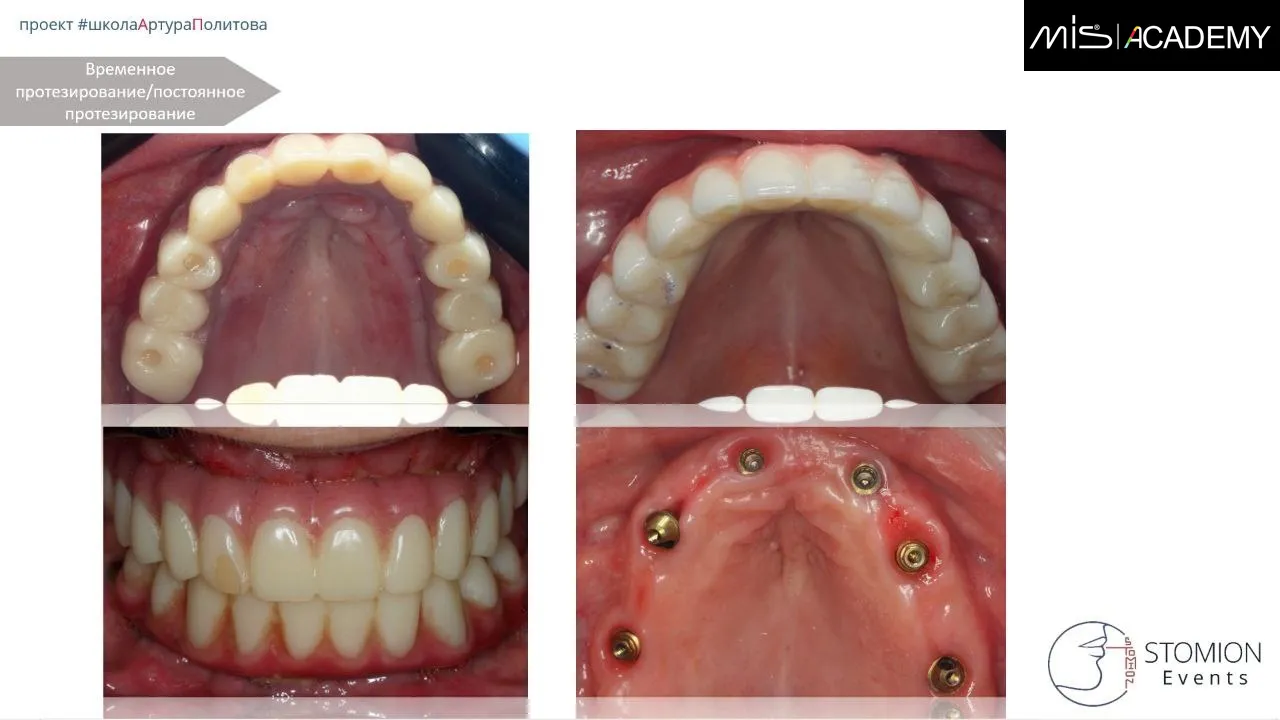

— Пациент передан ортопеду для ранней нагрузки.

— Через 5 дней нагрузка фрезерованной конструкцией.

С 6-го месяца изготовление постоянной конструкции FP-3, диоксид циркония с нанесением, с фрезерованным, анодированным титановым каркасом с уровня мультиюнитов и коннектов.